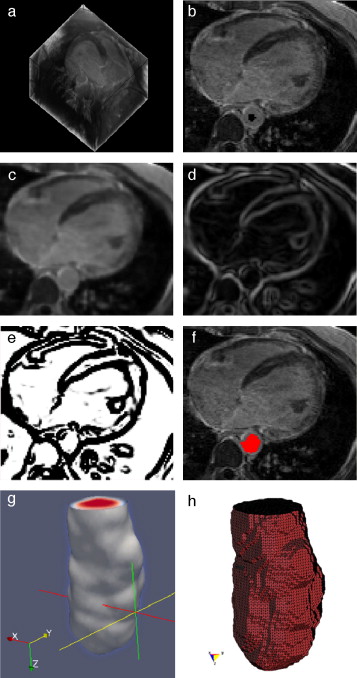

Las IRM del ventrículo izquierdo se caracterizan porque la fuerza del gradiente en el endocardio es por lo general diferente a la del epicardio. Asimismo, el miocardio es fuertemente influenciado por inhomogeneidades en escala de grises responsables de los cambios locales en la media y la varianza de los tejidos. Considerando estas peculiaridades, es necesario utilizar más de una sola técnica en las etapas de preprocesado y segmentación. El flujograma de algoritmos utilizado es presentado en la figura 14 . Las técnicas son detalladas a continuación.

3.1.1. Preproceso

Para conseguir reducir el ruido de las imágenes sin atenuar las zonas de interés y resaltar adecuadamente las estructuras que conforman el corazón se necesitaba de una técnica de filtrado con preservación de bordes. El filtro de difusión anisotrópica comentado en el apartado 2.2.1 resultó ser ideal para este tipo de tareas. Como siguiente paso, se aplicó el cálculo del módulo gradiente sobre la imagen filtrada, lo cual permitió diferenciar de mejor manera los contornos de las estructuras del corazón.

3.1.2. Segmentación

Segmentar el volumen del ventrículo izquierdo puede resultar una tarea no tan complicada si se combinan técnicas de segmentación adecuadas para extraer estructuras grandes y bien definidas. En este caso, se obtuvieron mejores resultados al combinar dos técnicas de segmentación muy utilizadas en este tipo de tareas. En primer lugar se aplicó el algoritmo Watershed en la imagen gradiente, obteniéndose una imagen en escala de gris con las regiones uniformes etiquetadas por una intensidad de gris diferente para cada segmento obtenido. Watershed tiene la desventaja de producir sobre-segmentación si es aplicado sobre imágenes ruidosas y niveles de gris poco uniformes, sin embargo, esta dificultad fue superada al aplicar esta técnica sobre la imagen preprocesada. Posteriormente se utilizó la técnica de umbralización para determinar el umbral (o umbrales) que conforman la zona del ventrículo izquierdo, entre el conjunto de segmentados etiquetados.

3.1.3. Remuestreo y exportación a CAD

En el siguiente paso, se realizó el remuestreo del modelo geométrico segmentado empleando dilatación morfológica con un elemento estructural en forma de esfera de radio 3 × 3 × 3 . Esta tarea fue necesaria para suavizar superficies superpuestas y rellenar posibles agujeros generados durante la segmentación. Este modelo fue guardado en formatos legibles por software de visualización y herramientas CAD como GiD, ParaView, Autodesk Inventor y Abaqus.

3.1.4. Pruebas de discretización

En la figura 15 se presentan los resultados obtenidos por cada etapa de procesamiento en IRM cardiovascular. Las imágenes médicas utilizadas tienen formato DICOM [39] , con 59 cortes de tamaño 192 × 192 pixels, voxel spacing: 1,5625 × 1,5625 × 2,5 mm . Por efectos de visualización, solamente se presenta uno de los cortes axiales de la imagen 3D.

Figura 15. Preproceso y segmentación el volumen del ventrículo izquierdo. (a) Corte axial de la IRM cardiovascular original. (b) Imagen (a) filtrada con difusión anisotrópica. (c) Imagen gradiente obtenida a partir de (b). (d) Imagen Watershed con segmentos etiquetados obtenida a partir de (c). (e) Selección del segmento del ventrículo izquierdo empleando umbralización. |

En la figura 16 se presenta el volumen final del ventrículo izquierdo con el inicio de la válvula aórtica (fig. 16 .a), el modelo final suavizado visualizado en ParaView (fig. 16 .b), el modelo en sólido visualizado en Autodesk Inventor (fig. 16 .c), el modelo en malla visualizado en GiD (fig. 16 .d) y el modelo discreto con los elementos finitos realizado con Abaqus (fig. 16 .e). Estos modelos han sido obtenidos a partir de IRM cardiovascular de un paciente con cardiopatía isquémica. Obsérvese que la protuberancia presente en la zona superior derecha del ventrículo izquierdo constituye una zona de necrosis conocida como cicatriz isquémica, la cual es alojada en el músculo del miocardio.

Figura 16. Vista tridimensional de ventrículo izquierdo. (a) Volumen original visualizado con ParaView. (b) Volumen original suavizado con morfología matemática visualizado con ParaView. (c) Sólido del volumen generado con Autodesk Inventor. (d) Mallado del volumen generado con GiD. (e) Modelo discreto con el método de elementos finitos generado con Abaqus empleando condiciones de contorno de prueba. |